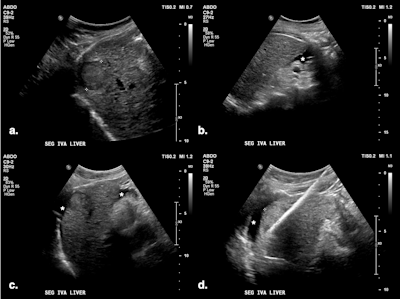

(A) Targeted HCC in segment IV-A near the diaphragm. (B) Artificial ascites (*) created using a 6.3 Fr Dawson-Mueller catheter inserted along the inferior margin of the left hepatic lobe. (C) Satisfactory distribution of ascites beneath the diaphragm. (D) Microwave antenna inserted at the target, with mechanical leveraging performed to further accentuate the gap between the liver and diaphragm.

Ultrasound-guided puncture at the peritoneal interface uses the liver, gallbladder, or stomach walls as a reference, and a catheter is deployed via a direct method or the Seldinger technique.

Di Muzio and colleagues prefer the 6.3 Fr Dawson-Mueller catheter for creating artificial ascites, but alternatives include a 14-20 G Chiba needle, One-Step Centesis Catheter, or a 5 Fr vascular catheter/sheath. They use a 1 L saline bag with a pressure cuff to expedite the infusion process, and the fluid distribution and liver displacement are monitored with ultrasound. There is no consensus on how thick the layer of fluid separating the structures should be, with the literature reporting between 5 and 10 mm.

This procedure uses a microwave antenna to displace the liver away from at-risk structures, usually in combination with artificial ascites, enhancing the protection of adjacent viscera against thermal injury. It can be useful in patients with adhesions.

"Mechanical displacement technique involves tilting the microwave needle handle to shift the liver away, thereby creating a wider gap between the ablation zone and organs at risk of collateral thermal injury," the authors stated. "When treating cirrhotic livers, which are typically stiff and smaller in volume, leveraging techniques can achieve significant displacement."